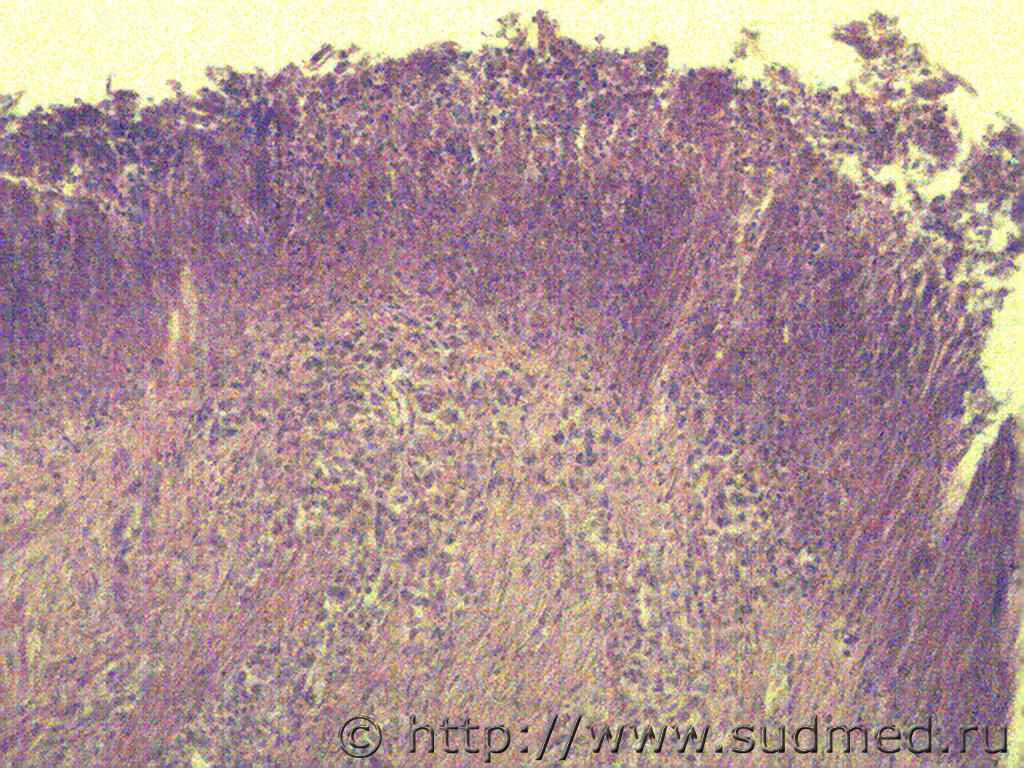

Первые две: ганглионеврома надпочечника (гистологич.находка, случай ДТП)